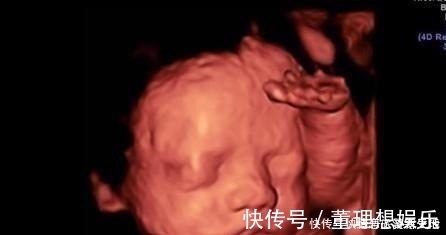

1.实时观察胎儿动态运动,检查胎儿生长发育情况。在怀孕期间,孕妈妈可以通过四维彩超得知胎儿在宫内的一些动态情况。比如说,通过四维彩超能够清楚的看到胎儿在宫内吞吐羊水,眨眼睛,吮吸手指,做鬼脸等动作。医生还可以通过四维彩超更清楚的看得到胎儿的发育情况,比如说血管畸形,体表畸形,内脏畸形等等,提前得知胎儿是否有唇裂,脊柱裂,骨骼发育不良,先天性心脏病等疾病,做到早知道早干预早治疗。2.图像清晰逼真。四维彩超相对于三维彩超更高清更精确,所以看起来更清晰,很多孕妈妈在做四维的时候就可以清晰地看到胎儿的五官,可以初步的判断一下胎儿到底长得像准爸爸还是准妈妈,所以,四维彩超也成为胎儿人生中的第一张照片。而不像二维一样,在大部分人看来就是黑坨坨的一片。